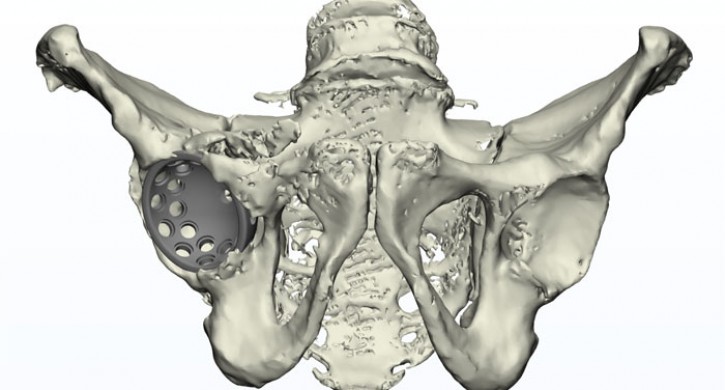

На снимке врачи увидели, что вертлужная впадина имеет нестандартную форму и размер, а головка сустава за это время полностью разрушилась.

«Для восстановления функции поврежденного сустава необходимо было провести эндопротезирование сустава. Если стандартный бедренный компонент может быть установлен при имплантации сустава, то тазовый эндопротез имплантировать с сохранением вертлужной впадины было практически невозможно. Нам необходимо было заместить дефект вертлужной впадины и создать условия для имплантации стандартного тазового компонента», – рассказал заведующий травматологическим отделением ГКБ № 1, врач-травматолог, ортопед Александр Троценко.

Помогли травматологам специалисты из Новосибирска, которые по заданным размерам, на основе результатов рентген- и КТ-исследований, смоделировали индивидуальный 3D-имплант. За счет средств больницы был изготовлен имплант из титанового сплава методом послойного лазерного спекания. Травматологи зафиксировали «чашу» винтами к тазу, в нее установили стандартный эндопротез.